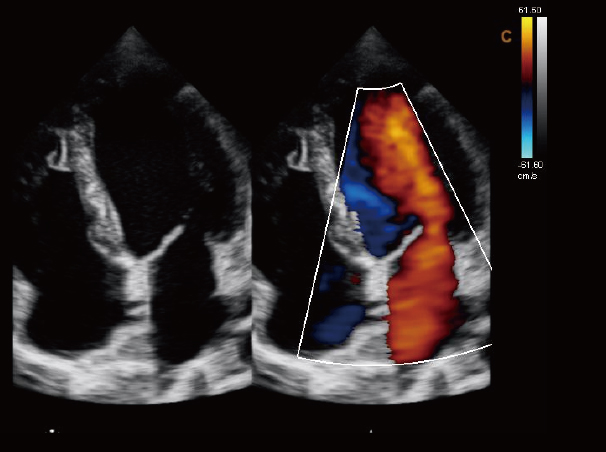

心脏,B/BC模式